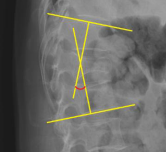

METHODS: Fifty-four patients (87 hips) with idiopathic osteonecrosis of the femoral head who were admitted to the Wangjing Hospital of the China Academy of Chinese Medical Sciences between January 2018 and June 2024 and a matched group of 162 patients (261 hips) were enrolled, including patients with steroid-induced osteonecrosis of the femoral head, alcohol-induced osteonecrosis of the femoral head, and patients without obvious hip joint disease. Four acetabular morphological parameters were measured on anteroposterior pelvic radiographs using standardized imaging methods: center-edge angle, Sharp angle, acetabular depth ratio, and acetabular head index.

RESULTS AND CONCLUSION: (1) The central-edge angle in the idiopathic osteonecrosis of the femoral head group was significantly smaller than that in the matched group [(27.4±4.5)° vs. (32.4±5.7)°], and the Sharp angle in the idiopathic osteonecrosis of the femoral head group was significantly larger than that in the matched group [(40.2±3.5)° vs. (38.7±2.9)°]. The acetabular depth ratio (276.4±33.3 vs. 319.3±31.6) and acetabular head index (82.4±5.1 vs. 85.4±4.2) in the idiopathic osteonecrosis of the femoral head group were significantly smaller than those in the matched group (all P < 0.001). (2) Compared with the steroid-induced osteonecrosis of the femoral head subgroup, the idiopathic osteonecrosis of the femoral head group had a smaller central-edge angle [(27.4±4.5)° vs. (33.0±5.2)°] and a larger Sharp angle [(40.2±3.5)° vs. (38.7±3.1)°], lower acetabular depth ratio and acetabular head index (all P < 0.05). (3) Compared with the alcoholic osteonecrosis of the femoral head subgroup, the idiopathic osteonecrosis of the femoral head subgroup also showed a smaller center-edge angle [(27.4±4.5)° vs. (32.7±5.4)°], a larger Sharp angle [(40.2±3.5)° vs. (38.7±3.0)°], and a lower acetabular depth ratio and acetabular head index (all P < 0.05). These results suggest that patients with idiopathic osteonecrosis of the femoral head have characteristic acetabular undercoverage, manifested by a reduced center-edge angle, increased Sharp angle, decreased acetabular depth ratio, and acetabular head index. This anatomical feature may serve as a potential risk factor for idiopathic osteonecrosis of the femoral head and aid in differentiating it from other subtypes of osteonecrosis of the femoral head. It is recommended to focus on acetabular morphology in clinical evaluations to optimize early screening and individualized intervention strategies.